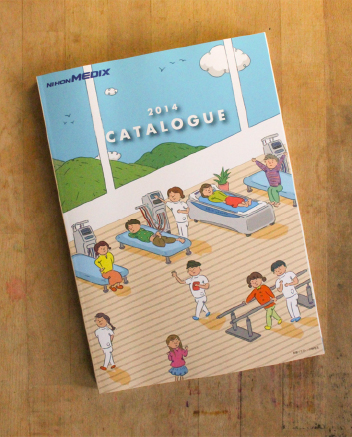

(株)日本メディックス / 2014カタログ

illustration

2013

client/(株)日本メディックス